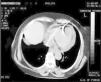

El diagnóstico de la perforación ventricular secundaria a electrodos de marcapasos la podemos identificar y confirmar con radiografía de tórax como lo observamos en nuestro caso, en el cual se encontraba el electrodo ventricular fuera de la cámara cardiaca. Otros métodos diagnósticos pueden ser el fluoroscopio, la ecocardiografía o TAC de tórax, encontrándose en esta última alteraciones de hasta el 15% de pacientes asintomáticos durante los controles postimplante del dispositivo10,23,24. En el ecocardiograma tridimensional podemos obtener una mayor precisión que en la TAC de tórax en la identificación de la perforación ventricular por electrodos, debido principalmente al efecto tomográfico conocido como «estrella» causado por los materiales del electrodo (figs. 8 y 9), haciendo difícil el diagnóstico. No existe consenso sobre criterios radiográficos diagnósticos universalmente aceptados entre los grupos de radiólogos, por esto la correlación clínica nos orienta. Todos estos estudios orientan al diagnóstico, pero la no evidencia del electrodo fuera del corazón no nos descarta la complicación, como sucedió en nuestro caso donde hubo una migración del electrodo de fijación activa auricular derecho con posterior perforación del ventrículo ipsilateral, lo cual nos muestra una complicación aún más infrecuente debido a la perforación ventricular por el electrodo ubicado en la aurícula17,25,26.

Tomografía computarizada de tórax, en la que observamos el electrodo de fijación activa a través del corazón, indicando su trayectoria con las flechas amarillas en el ventrículo derecho y pericardio25.

Tomografía computarizada de tórax en corte axial con el signo de la «estrella» generado por el electrodo17.